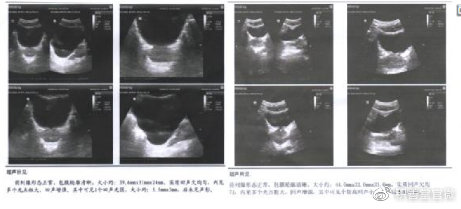

他传来的检查单可见前列腺形态正常,包膜轮廓清晰,大小约39.6*31*24mm,实质回声欠均匀,内可见多个光点粗大,回声增强。其中可见一个强回声光团,大小约5.5*3mm,后未见声影。

从B超检查上来看,患者的腺体,上下径有轻微增大,并有钙化病灶形成。

他的B超可见前列腺形态正常,包膜轮廓清晰,大小约44mm*32mm*23mm,实质回声欠均匀,内可见多个光点粗大,回声增强。其中可见个别高回声光点,后未见声影。

患者B超检查与上次对比腺体有增大,病灶已经比之前变淡,说明他之前的治疗效果很好。

他又进行了四个疗程的治疗,2019年7月,在他传回来的B超检查单上只有两个病灶,还都膨大变淡了。

樊某停止了治疗,2020年8月,他回传过B超检查单给医生助理,他的腺体形态正常,大小适合,无病灶形成,无症状复发。

他认真完成了崩解病灶的治疗,治疗前后的B超检查可以看到腺体病灶明显回弹,腺体软化;钙化灶被崩解。